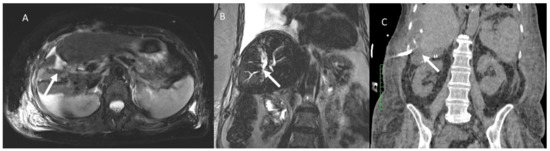

- Granata, V.; Fusco, R.; Catalano, O.; Piccirillo, M.; De Bellis, M.; Izzo, F.; Petrillo, A. Percutaneous Ablation Therapy of Hepatocellular Carcinoma with Irreversible Electroporation: MRI Findings. Am. J. Roentgenol. 2015, 204, 1000–1007. [Google Scholar] [CrossRef] [PubMed]

- Granata, V.; Fusco, R.; Salati, S.; Petrillo, A.; Di Bernardo, E.; Grassi, R.; Palaia, R.; Danti, G.; La Porta, M.; Cadossi, M.; et al. A Systematic Review about Imaging and Histopathological Findings for Detecting and Evaluating Electroporation Based Treatments Response. Int. J. Environ. Res. Public Health 2021, 18, 5592. [Google Scholar] [CrossRef] [PubMed]

- Granata, V.; Castelguidone, E.D.L.D.; Fusco, R.; Catalano, O.; Piccirillo, M.; Palaia, R.; Izzo, F.; Gallipoli, A.D.; Petrillo, A. Irreversible electroporation of hepatocellular carcinoma: Preliminary report on the diagnostic accuracy of magnetic resonance, computer tomography, and contrast-enhanced ultrasound in evaluation of the ablated area. Radiol. Med. 2016, 121, 122–131. [Google Scholar] [CrossRef]